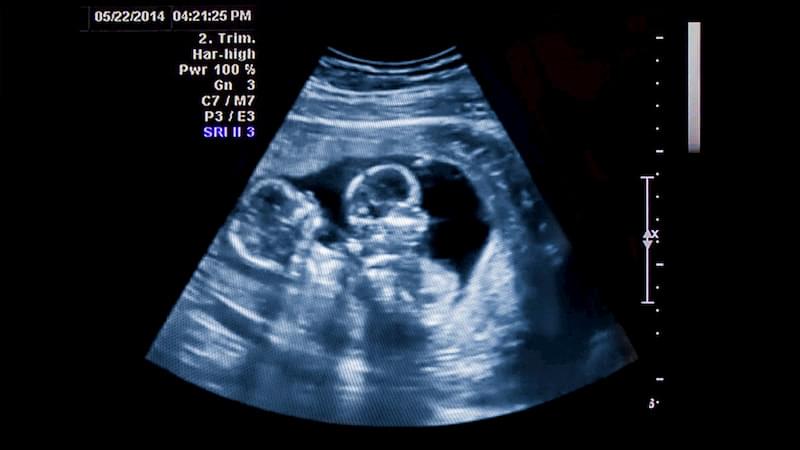

В первые 6-8 недель врач на УЗИ уже наверняка скажет тип близнецов (количество плаценты и амниотических пузырей). Это важные данные, которые нужно определить поскорее.

УЗИ также проводятся чаще: в зависимости от типа двойни и количества плацент – это 1 раз в 4 недели или каждые 2 недели.